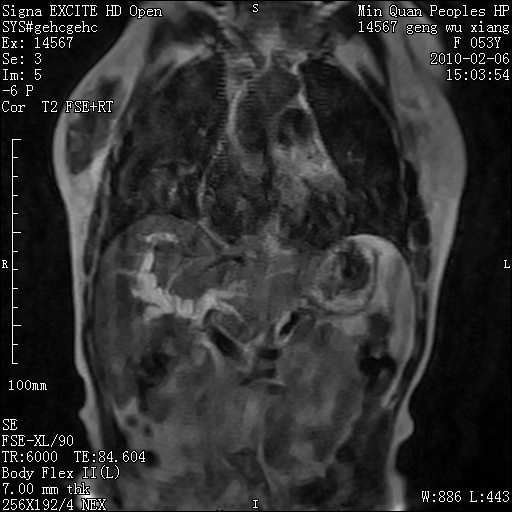

标题: MRI2762:胆道梗阻原因?

f,53y,全身黄染多日。

高位胆道梗阻 胆管癌可能性大

支持 高位胆道梗阻 胆管癌可能性大。